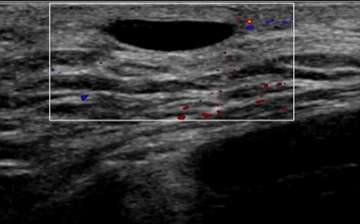

The ultrasound above demonstrates a well-circumscribed, anechoic, parallel, and avascular tubular structure with well-defined borders, consistent with a dilated duct. The opposite breast also revealed similar dilation of the ducts, this symmetry is reassuring and benign. Features of ductal dilation which are concerning (and may warrant biopsy) include unilateral breast ductal dilation or a focal ductal dilation in a breast with otherwise normal sized ducts. Furthermore, a dilated duct which is not anechoic (fluid filled or with internal soft tissue nodularity), with an irregular shape, or with indistinct margins are also more suspicious.

Using Doppler ultrasound, the amount of blood flow to an area of interest can be assessed and compared to surrounding tissue. Increased vascularity may suggest inflammation (i.e. infection such as mastitis) or malignancy. Doppler is especially helpful when evaluating for blood flow to cystic lesions, which may suggest a solid component (vascular) rather than debris within a cyst (avascular). In Figure 4, the anechoic structure was avascular on Doppler, consistent with a cystic structure (dilated duct).